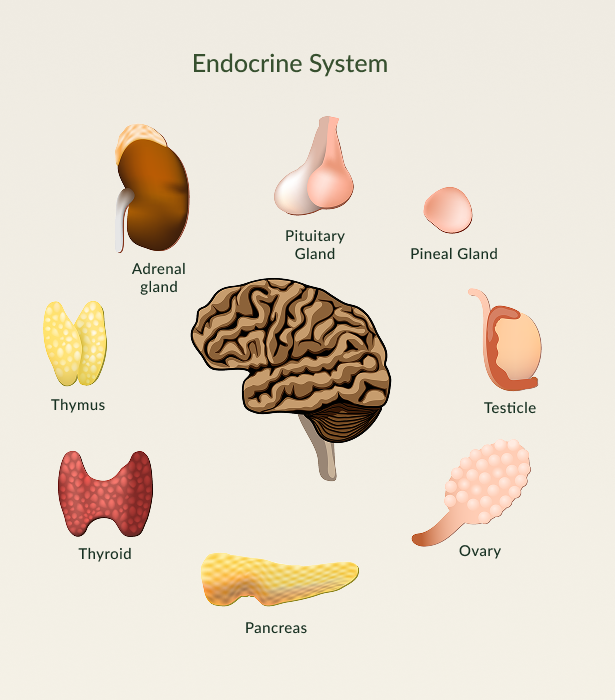

What Does an Endocrinologist Do?

An endocrinologist is a medical specialist who diagnoses and treats hormonal imbalances and problems related to the endocrine system—the network of glands that regulate metabolism, growth, reproduction, and mood.

What Is the Endocrine System?

The endocrine system includes glands like:

- Hypothalamus – regulate hormones related to hunger, thirst, and sleep

- Thyroid – regulates metabolism and energy

- Pancreas – controls blood sugar (insulin)

- Adrenals – manage stress hormones and blood pressure

- Pituitary – the “master gland” that controls others

- Ovaries/Testes – regulate sex hormones

Parathyroid – balances calcium levels